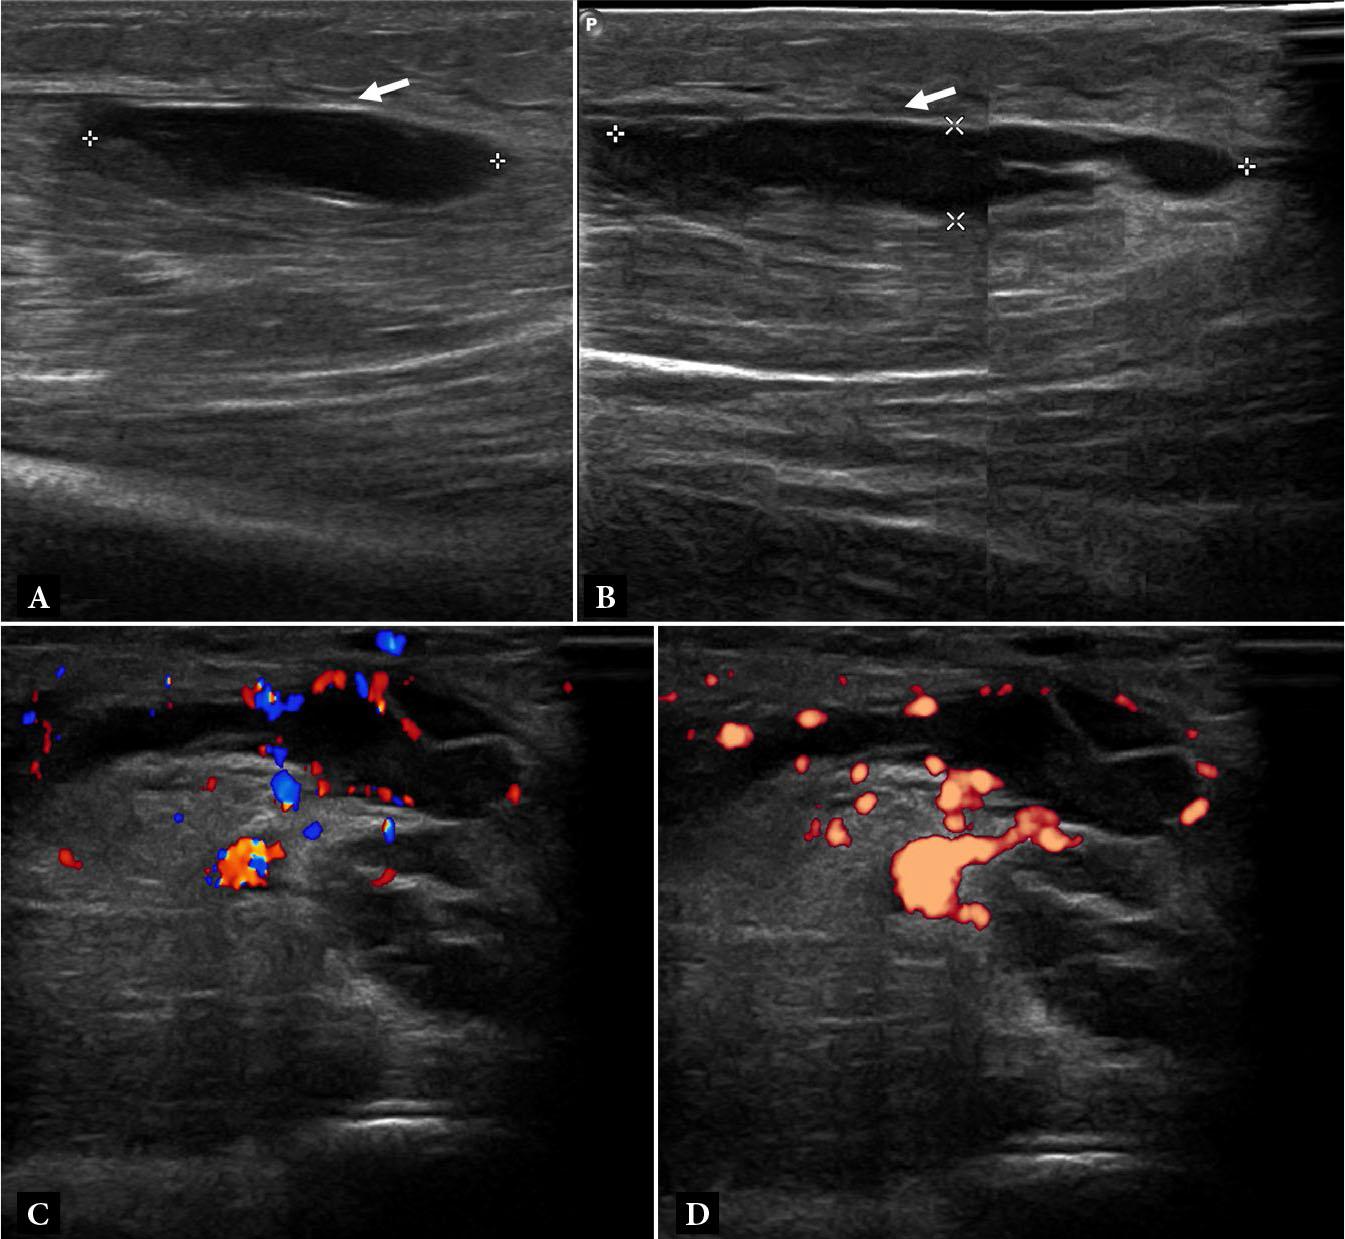

Fig. 3.